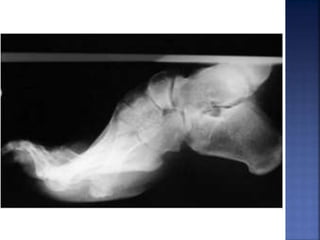

 Deformidad en pies: Pie cavo y dedos en

martillo.

 Molestias alcaminar.  Debilidad muscular en pies.  Deformidad en pies: Pie cavo y dedos en martillo.  Degeneración muscular.  Pérdida de sensibilidad en: pies, piernas, manos y antebrazos.